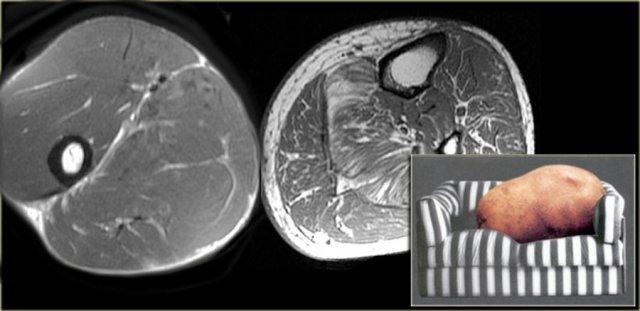

Hình bên trái là một ví dụ, lưu ý các thay đổi viêm ở các cơ lớn vùng mông.

Sau khi ngừng thuốc, đau cơ sẽ biến mất trong khoảng 2 tuần, tuy nhiên MRI vẫn còn cho thấy bất thường cho đến khoảng một tháng sau đó.

Thời điểm tốt nhất để chụp MRI theo dõi là khoảng 6 tuần sau khi ngừng thuốc.

Đây là bệnh nhân cao tuổi có tăng cholesterol máu được chỉ định dùng Lipitor.

Bệnh nhân xuất hiện đau nhức cơ, CPK tăng nhẹ.

Các thay đổi khá tinh tế, chúng ta thấy các ổ tụ dịch quanh mạc cơ, ở rìa ngoài của cơ (ngoại mạc cơ).

Ngoài ra còn có thay đổi da tối thiểu.